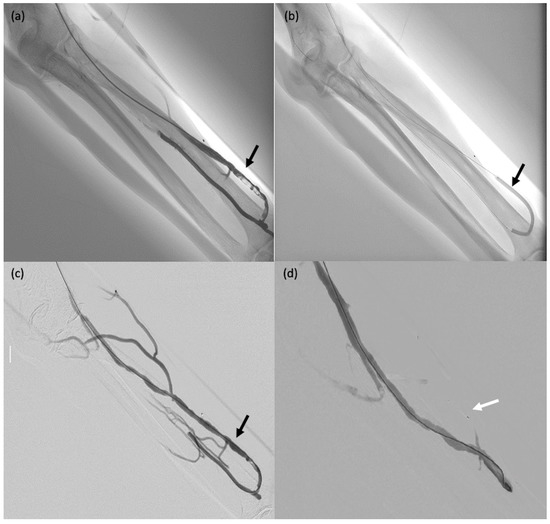

The clinical success rate was assessed based on the 28 patients left after the exclusion of the five patients with liver cancer. Embolisation was successful with no recurrence during follow-up in 24 patients. In patient #10 with bleeding after partial right nephrectomy for a tumour and a false aneurysm of the superior polar artery, successful MVP embolisation was followed by recurrent bleeding caused by the development of collaterals, which were occluded using glue. In patients #19, #23 and #24, who had acute anaemia due to bleeding from a false aneurysm of the gastroduodenal artery with failed endoscopic treatment, initially successful embolisation combining MVPs, coils and glue was followed by recurrent bleeding due to collateral development; further embolisation with other agents and medical and surgical management ensured control of the bleeding.

Figure 5. This 65-year-old female patient (#10) started experiencing severe lumbar pain six days after partial nephrectomy for renal cancer with renal artery clamping. Her haemoglobin level dropped by 3 g/dL and her haemodynamics were unstable. Active postoperative bleeding was suspected, and she was taken to the computed tomography suite. (a,b) Active retroperitoneal bleeding (false aneurysm) (arrow). (ce) Angiography showing a false aneurysm of the superior polar artery of the right kidney ((c), arrow), which was embolised using an MPV-3Q ((d), arrow); stenting of the renal artery (clamp injury) ((e) arrow). (f) CT two days after embolisation: there was no active bleeding and the MVP-3Q and stent were properly positioned (arrow).